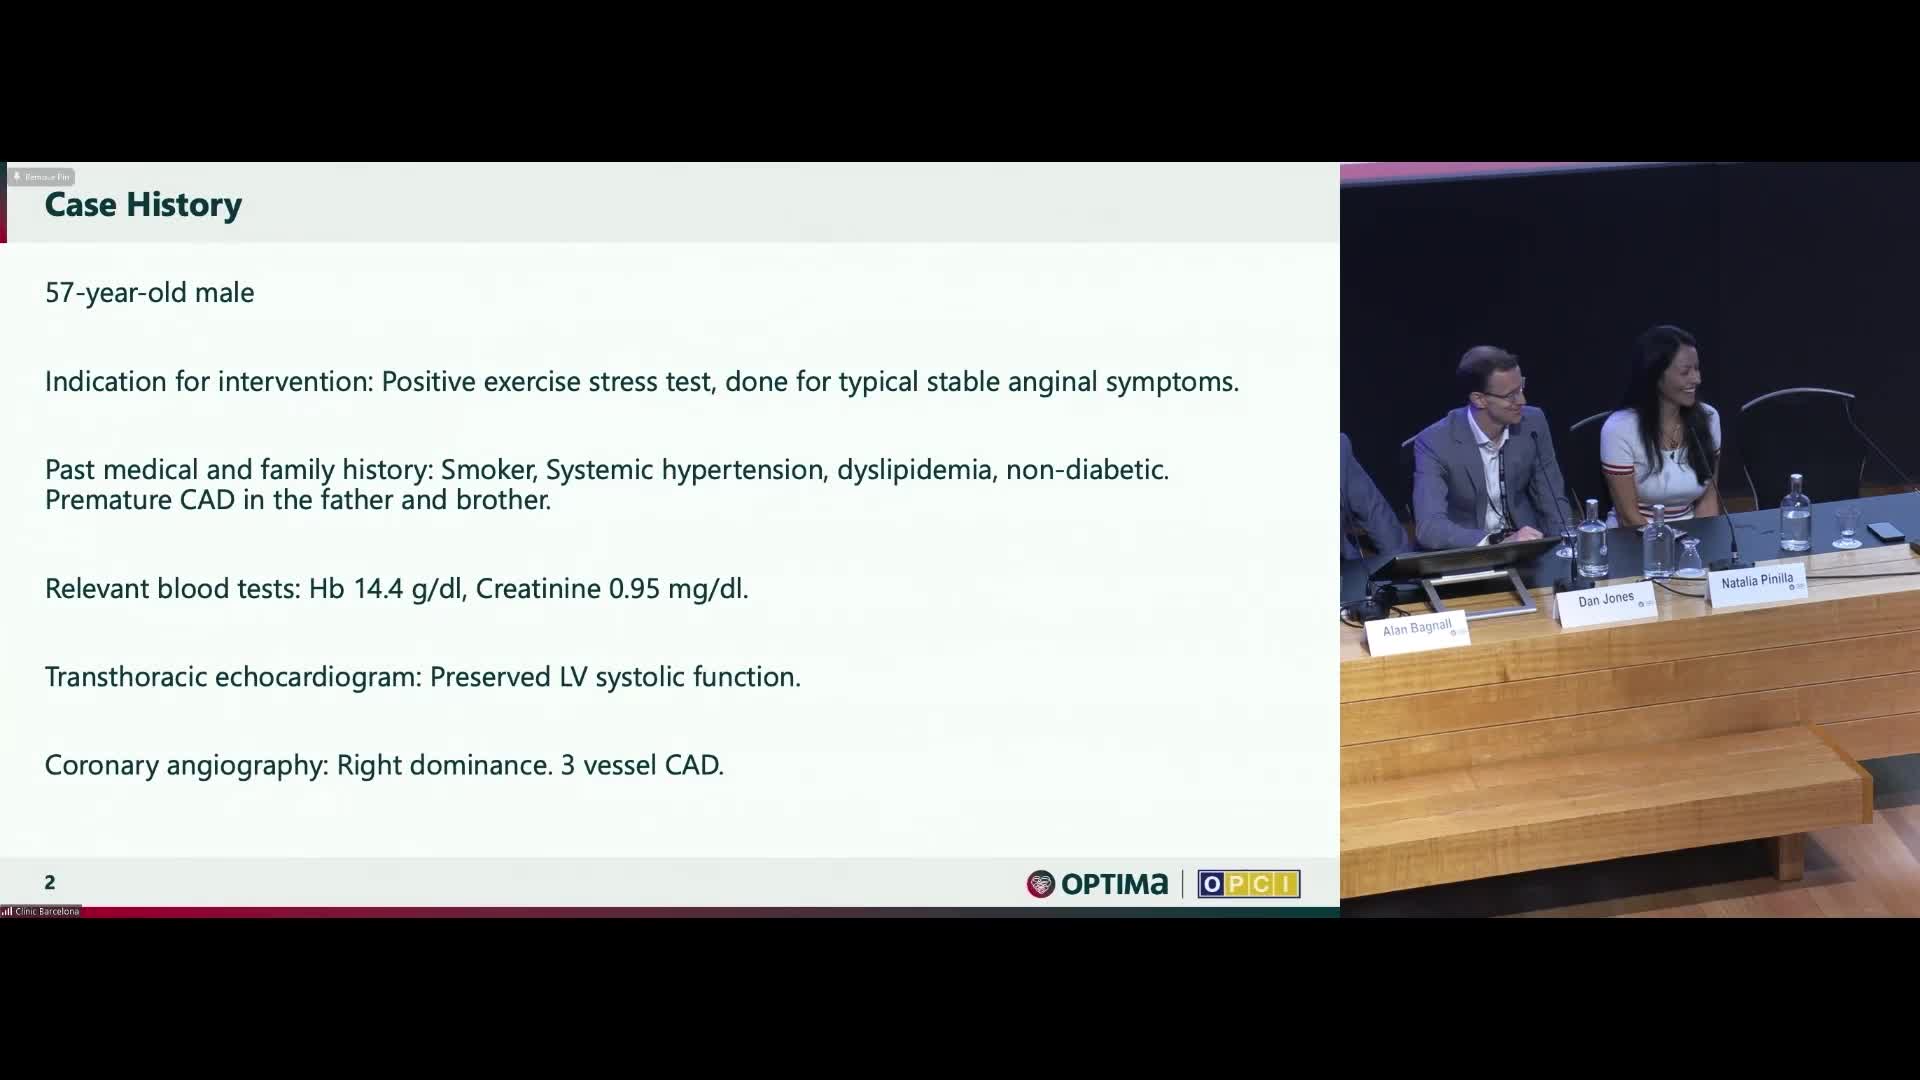

Session 1: Pre-procedure planning – are we lost without a map?